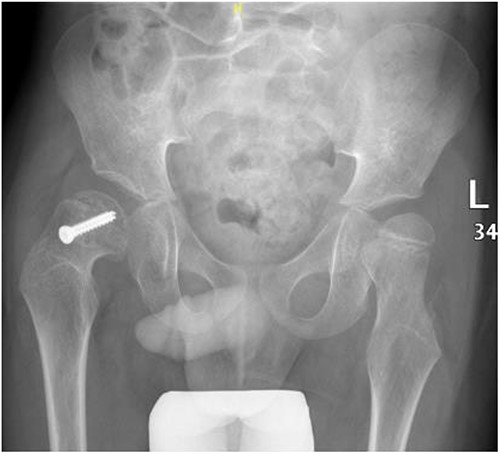

A 5-year-old independent ambulatory Middle Eastern boy with CP who was born preterm and developed grade III intraventricular haemorrhage and periventricular leucomalacia and was on AEDs, including valproic acid (VPA) and levetiracetam (LEV), for >3 years and was controlled over the last year (no history of seizure attack) presented to the emergency room (ER) with right hip pain and inability to bear weight for 4 weeks; the patient had no history of fever or trauma. Physical examination shows a thin, the weight is 12 kg, the height is 101 cm, vital signs within the normal range, tenderness over the right hip, and external rotation of the right hip, with restricted hip mobility. A radiological study was performed ~3 months before the patient presented to the ER for follow-up examination of a left hip coxa valgus deformity with no apparent abnormalities in the right hip (Fig. 1). Initial imaging studies conducted in the ER showed an anterior–posterior view of the pelvic radiograph, revealing Klein’s line [13] not intersecting the capital femoral epiphysis (Fig. 2), and frog-leg lateral view radiograph of the right hip (Fig. 3) confirmed SCFE and Southwick’s slip angle [13] of ~50° (moderate). Laboratory findings were clear for endocrine and renal diseases or infection, except for low vitamin D (total 25-OH Vitamin D: 43.4 nmol/L), suggesting vitamin D insufficiency. The diagnosis was confirmed with clinical and radiological studies as right-sided unstable SCFE requiring surgery. Surgical intervention was performed with percutaneous in situ fixation using a single fully threaded 4.5-mm cannulated screw (Fig. 4). Postsurgical rehabilitation included non-weight-bearing right lower extremities for 6 weeks. Regular follow-up with serial radiology studies showed stable fixation with no migration of screw or further slippage at 6 weeks (Fig. 5) and 3 (Fig. 6), 15 (Fig. 7), and 36 months (Fig. 8). During follow-up, a painless range of motion in the right hip was observed, with full weight-bearing and resumption of his usual activities with no complaints.

Pelvic anterior–posterior radiograph showing coxa valga deformity in the left hip.